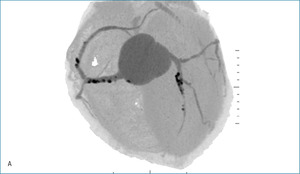

Rycina 1. Badanie tętnic wieńcowych metodą tomografii komputerowej. A. Rekonstrukcja MIP Inwers (maximum intensity projection) – widoczne liczne zwapnienia w lewej tętnicy wieńcowej oraz krytyczne zwężenie w jej środkowym segmencie. B. Rekonstrukcja VR (volume rendering) – krytyczne zwężenie środkowego segmentu lewej tętnicy wieńcowej oraz gałęzi diagonalnej. C. Warstwa poprzeczna (axial) – widoczna blaszka niskiej gęstości wypełniająca światło segmentu środkowego lewej tętnicy wieńcowej.

– Gałąź przednia zstępująca (GPZ): segment 6 z blaszką niskiej gęstości ~30% (remodeling dodatni ściany!); segment 7 – długa blaszka (12-15 mm) niskiej gęstości z remodelingiem dodatnim ściany, zwężająca w części środkowej krytycznie światło ~95%. Referencja proksymalna 4,3 mm, dystalna 2,1 mm; segment 7 za zmianą i segment 8 z wielopoziomowymi blaszkami niskiej gęstości ~30% (ryc. 1).